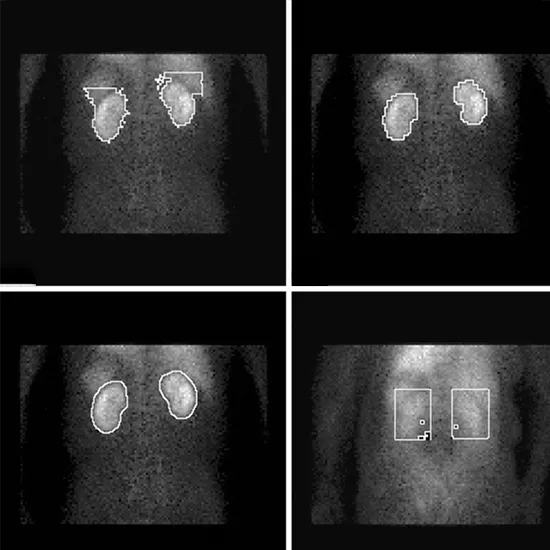

Renal DTPA scanning is a method of diagnosing and evaluating kidney function. It entails administering radiopharmaceutical material intravenously in order to assess the drainage pattern of the kidneys and determine if any areas are not functioning properly.

You'll be placed in front of the Gamma Camera and given a small injection of a radioactive tracer. This injection should not make you feel any different and will allow images of your kidneys to be taken. Images are taken continuously for 20-40 minutes beginning at the time of injection.